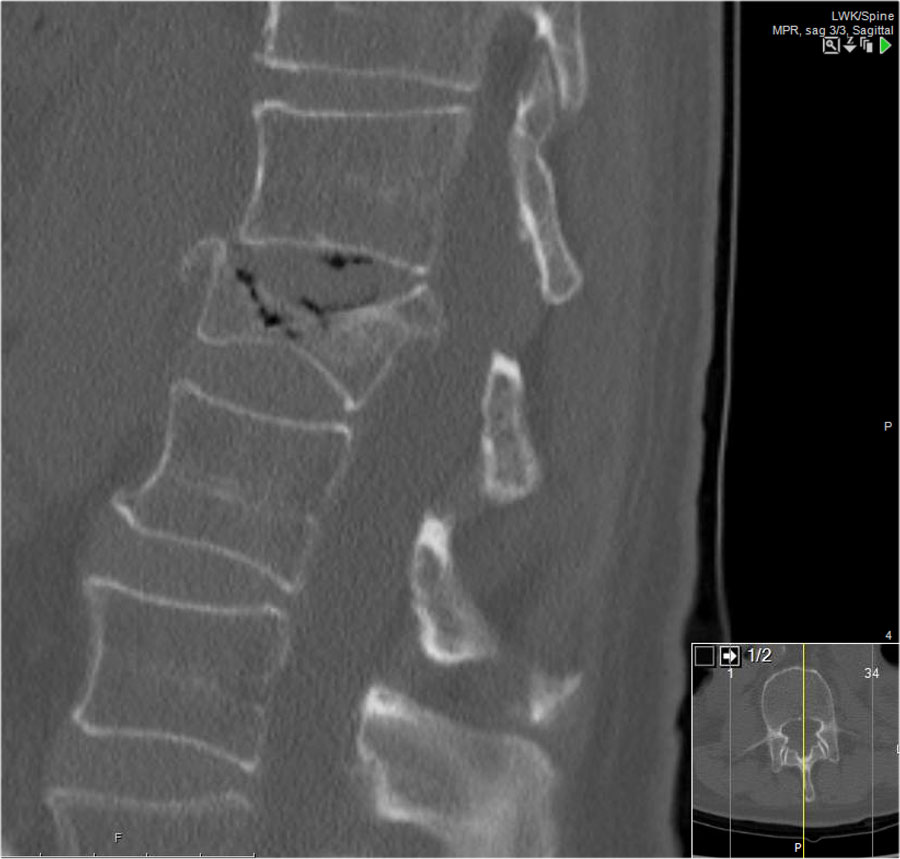

Giãn rộng khoảng cách liên cuống (interpedicular distance)

Giãn rộng khoảng cách liên cuống, thường là hệ quả của đường gãy theo mặt phẳng đứng dọc, gặp trong 80% các trường hợp gãy vỡ.

Hình chiếu bên cho thấy các đặc điểm điển hình của gãy vỡ.

Trên hình chiếu thẳng (AP), lưu ý sự giãn rộng kín đáo của khoảng cách liên cuống so với các tầng trên và dưới.

CT axial và MRI trên cùng một bệnh nhân cho thấy mảnh xương di lệch đang chèn ép vào bao màng cứng (thecal sac).

Trên CT và MRI mặt phẳng đứng dọc, không có dấu hiệu tổn thương dây chằng phía sau.

Dây chằng dọc trước bị đứt.

Khớp mặt bên phải trông hơi giãn rộng trên CT và có dịch trong khớp trên MRI.

Nếu có nhiều dịch trong khớp, chúng ta nên xếp loại là không xác định.

Trong trường hợp này, chúng ta chưa chắc chắn.